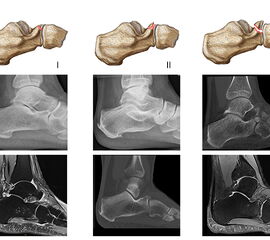

Die Klassifikation der PAC Verletzung erfolgt nach Degan et al. 3. Diese unterscheidet insgesamt drei Fraktur-Typen anhand der Fragment-Größe und der artikulären Beteiligung.

Zum Lesen der Bildbeschreibung und zur Vollansicht bitte das Bild anklicken. Bild: M. Walther

Die Klassifikation nach Degan wurde bereits 1982 publiziert und basiert auf der Auswertung von konventionellen Röntgenaufnahmen von 25 Patienten 3.

Typ I: Nicht-dislozierte, extra-artikuläre Avulsionsfrakturen des Processus anterior.

Typ II: Dislozierte, extra-artikuläre Frakturen des Processus anterior.

Typ III: Große, dislozierte Frakturen mit Affektion des calcaneo-cuboidalen Gelenkes (CC-Gelenk).

Frakturen des Processus anterior calcanei sind in etablierten Kalkaneusfraktur-Klassifikationen (Sanders, Essex-Lopresti, Arbeitsgemeinschaft für Osteosynthesefragen (AO/OTA)) gar nicht oder nur am Rande erwähnt 252627. Diese Klassifikationen subsumieren die Frakturen des PAC unter den extra-artikulären Frakturen. Zwipp und Kollegen führten mit der „Integral Classification of Injuries“ (ICI) eine detaillierte Betrachtung der PAC Frakturen ein. Hier werden diese als artikuläre Verletzungen klassifiziert und zudem begleitende Bandverletzungen und die Fragment-Dislokation berücksichtigt 28. Eine Klassifikation - möglicherweise auf der Basis von CT-Bildern - in die die Fraktur-Lokalisation, die Fragment-Größe und -Dislokation sowie die Begleitverletzungen eingehen, wäre hilfreich, um sich dieser Frakturentität und der damit einhergehenden Behandlungsempfehlung weiter zu nähern. Die von Degan beobachteten extra-artikulären Frakturen im konventionellen Röntgen imponieren in CT und MRT als knöcherne Ausrisse des Lig. bifurcatum im Randbereich des Gelenks. Häufig finden sich aber auch bei kleinen Fragmenten eine intraartikuläre Komponente.